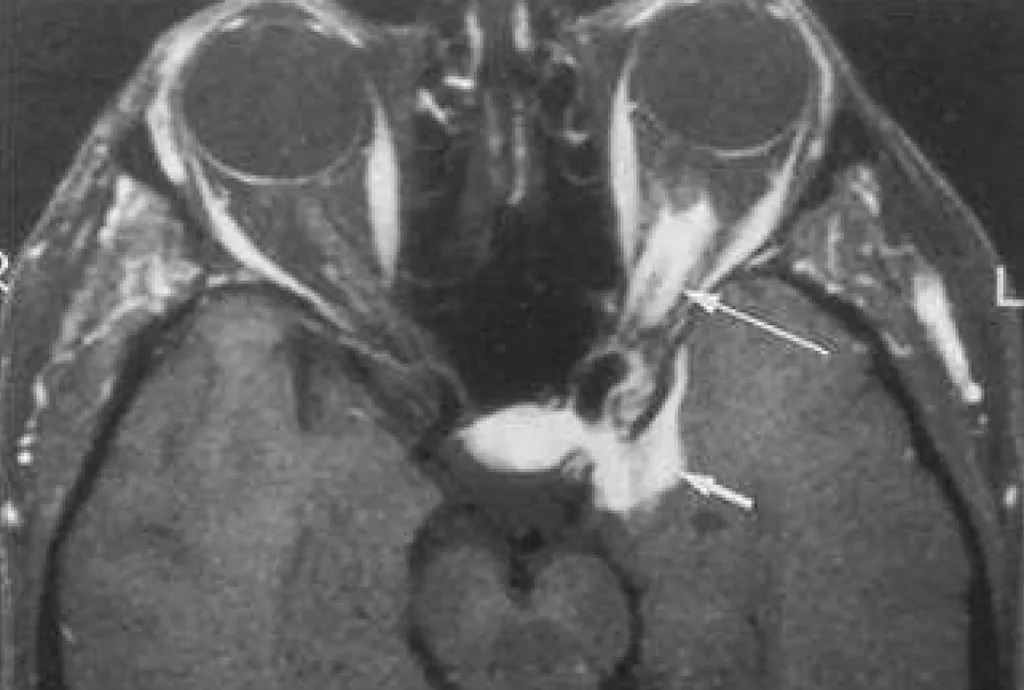

【108-2 醫學(六) 第72題】40歲女性患者,主訴幾個月來左眼視力逐漸減退,接受磁振造影檢查,圖為注射顯影劑後並且經過抑制脂肪處理的T1加權影像,圖中箭號所指最可能的病變是:

這題的解題核心在於辨識影像中左側視神經周圍呈現的「軌道徵象」(tram track sign),這是視神經鞘腦膜瘤的典型影像特徵。